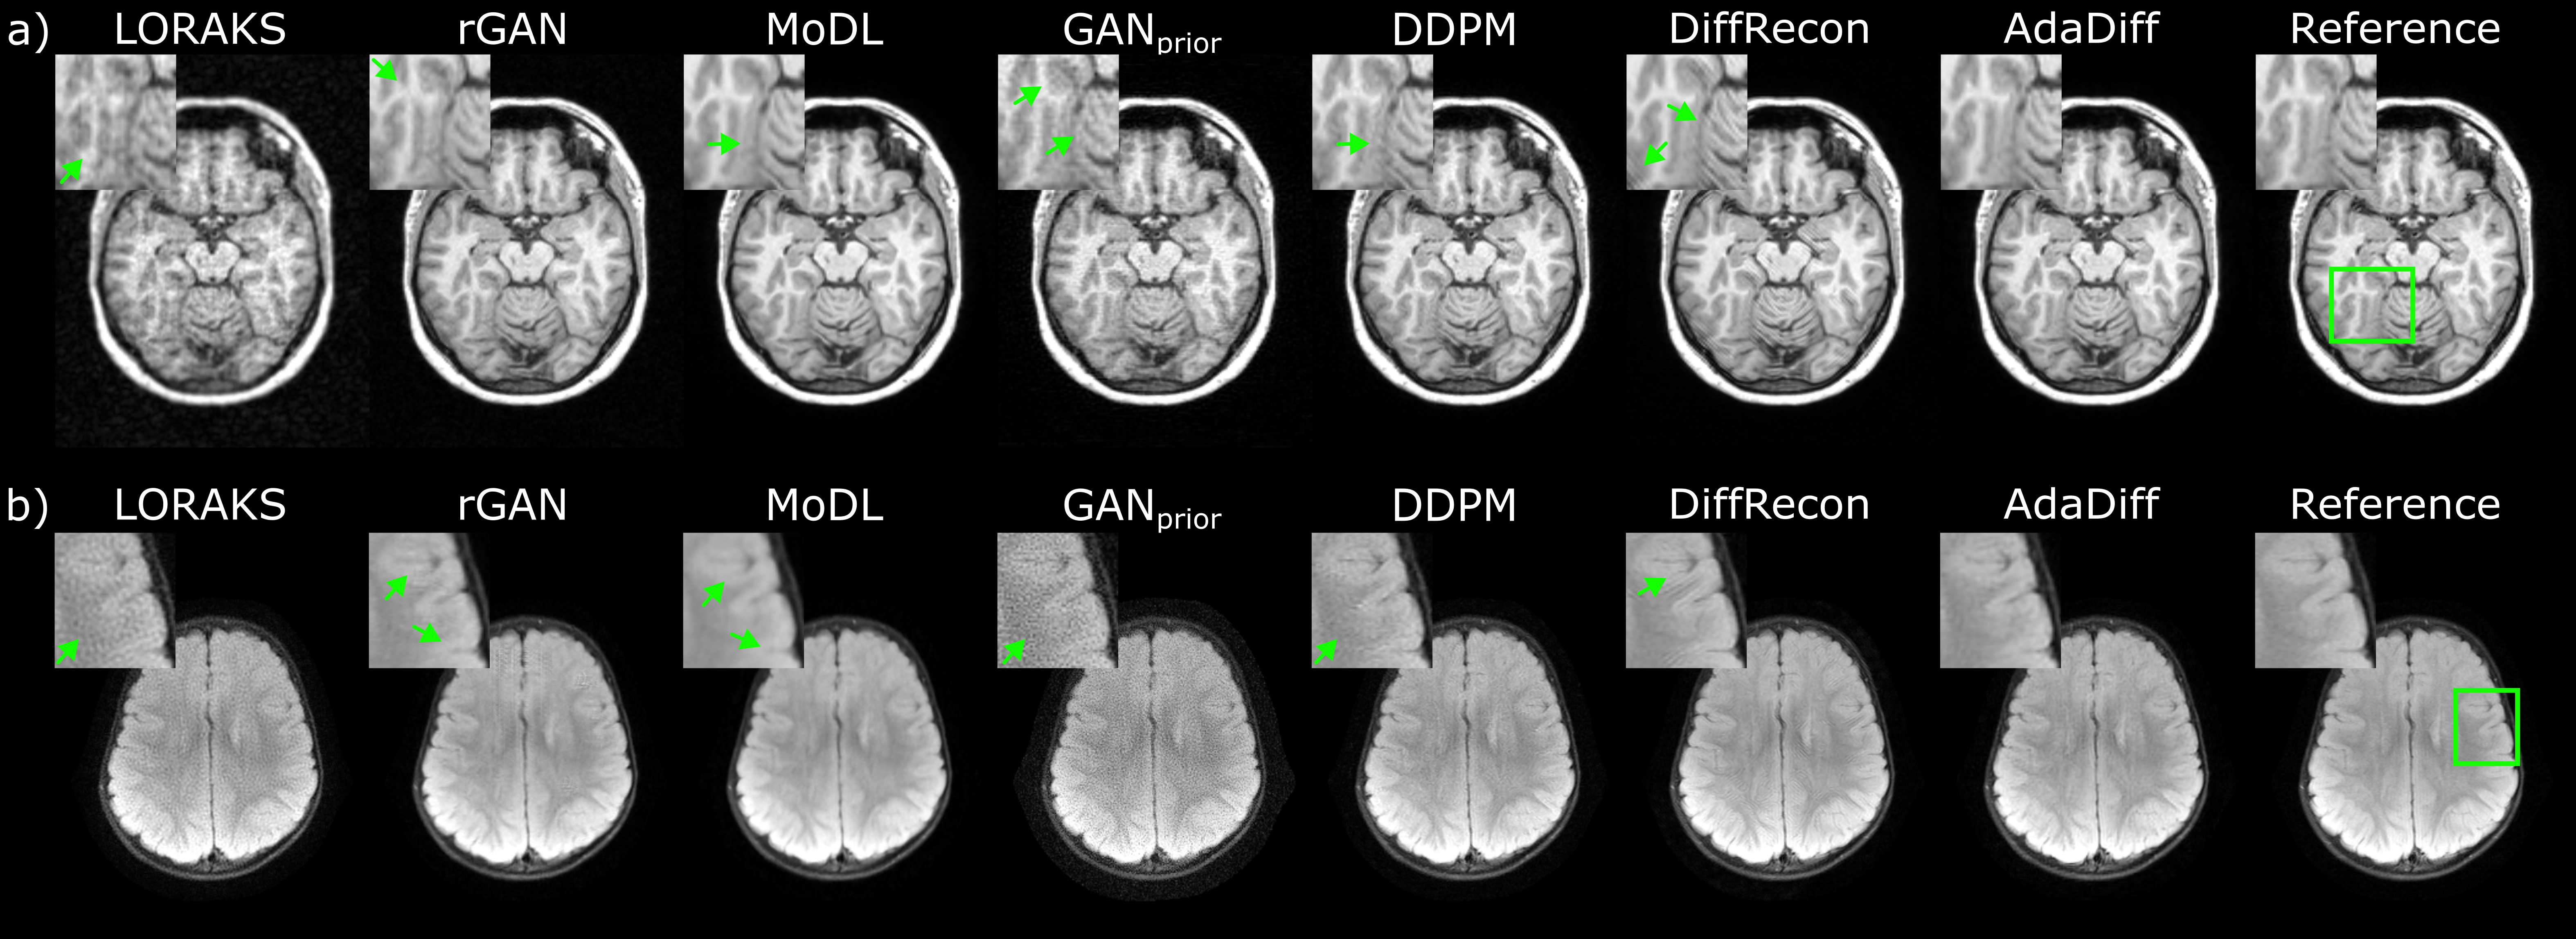

Fig. 5: Cross-domain reconstructions under domain shifts in the acceleration rate. Results are shown for (a) T2-weighted acquisitions at R=8x in IXI, and (b) T2-weighted acquisitions at R=12x in fastMRI. Reconstructed images are given along with the reference image derived from fully-sampled acquisitions, and zoom-in windows and arrows are included to highlight differences among methods. Conditional models were trained at R=4x. LORAKS and GANprior show high noise amplification, rGAN and MoDL show some residual reconstruction artifacts and spatial blurring. Among diffusion models, DDPM has relatively high noise and DiffRecon has local ringing artifacts. AdaDiff reconstructs images with low artifacts/noise and a closer appearance to the reference images.

We then demonstrated performance in cross-domain reconstructions where the MR image distribution was matched, albeit the imaging operator was mismatched between the training and test sets. To this end, several studies were conducted to examine the influence of varying operator attributes on reconstruction performance. First, we assessed the influence of acceleration rate by training conditional models at R=4x while testing all models at R=8x and R=12x. Note that unconditional models and LORAKS were not informed about undersampling during training. PSNR and SSIM for competing methods are listed in Table 3 for IXI, and in Table 4 for fastMRI. In IXI, AdaDiff achieves the highest performance across contrasts and acceleration rates (p<<0.05), except for DiffRecon that yields similar SSIM on T1 at R=8x. In fastMRI, AdaDiff again outperforms competing methods across contrasts and acceleration rates (p<<0.05), except for MoDL that yields similar SSIM on FLAIR at R=8x and higher SSIM on T1 at R=12x, and DiffRecon that yields similar PSNR on T2 at R=8x. On average, AdaDiff outperforms the traditional method by 4.9dB PSNR and 16.0% SSIM, conditional models by 2.3dB PSNR and 4.4% SSIM, the adaptive GAN by 6.8dB PSNR and 20.6% SSIM, and static diffusion models by 0.9dB PSNR and 1.5% SSIM. Note that, at R=8x, the performance benefit of AdaDiff over MoDL is 1.5dB PSNR, 2.3% SSIM under domain shift in acceleration rate, versus 0.3dB PSNR, 0.4% SSIM in within-domain reconstruction. This difference suggests that AdaDiff’s unconditional prior is more reliable against variations in acceleration rate compared to MoDL’s conditional prior. Representative reconstructions are displayed in Fig. 5. LORAKS and GANprior suffer from noise amplification, rGAN and MoDL shows residual aliasing artifacts and blurring. Similar to the within-domain case, DDPM has relatively high noise levels and DiffRecon shows local ringing artifacts in comparison to AdaDiff that maintains the closest appearance to the reference images.

Next, we assessed the influence of domain shifts in sampling trajectory and number of coils on reconstruction performance. Under fixed acceleration rate and number of coils, sampling trajectory was varied by training conditional models based on 2D undersampling patterns while testing all models on 1D undersampling patterns. Under fixed acceleration rate and sampling trajectory, number of coils was varied by training conditional models based on 5 virtual coils and testing all models on 10 virtual coils. PSNR and SSIM for competing methods are listed in Table 5 for both assessments. When the sampling trajectory is varied, AdaDiff achieves the highest performance among competing methods across tissue contrasts (p<<0.05), except for MoDL that yields higher SSIM on FLAIR, and DDPM that yields similar PSNR on FLAIR. When the number of coils is varied, AdaDiff yields higher performance across tissue contrasts (p<<0.05), except for MoDL that yields similar SSIM on FLAIR, and DiffRecon that yields higher performance on T2. On average, AdaDiff outperforms the traditional method by 5.0dB PSNR and 10.0% SSIM, conditional models by 1.6dB PSNR and 1.2% SSIM, the adaptive GAN by 7.2dB PSNR and 20.2% SSIM, and static diffusion models by 1.0dB PSNR and 2.0% SSIM. Note that, at R=4x in fastMRI, the performance benefit of AdaDiff over MoDL is 1.6dB PSNR, 1.2% SSIM under domain shift in sampling trajectory, 0.6dB PSNR, 0.2% SSIM under domain shift in number of coils, versus 0.5dB PSNR, 0.1% SSIM in within-domain reconstruction. These findings suggest that AdaDiff is notably more reliable than MoDL against shifts in the sampling trajectory, whereas it is similarly affected by shifts in the number of coils. Representative reconstructions are displayed in Fig. 6. LORAKS and GANprior suffer from noise amplification, rGAN and MoDL show residual aliasing artifacts and blurring. Similar to the within-domain case, DDPM has relatively high noise levels and DiffRecon shows local ringing artifacts in comparison to AdaDiff that maintains the closest appearance to the reference images.